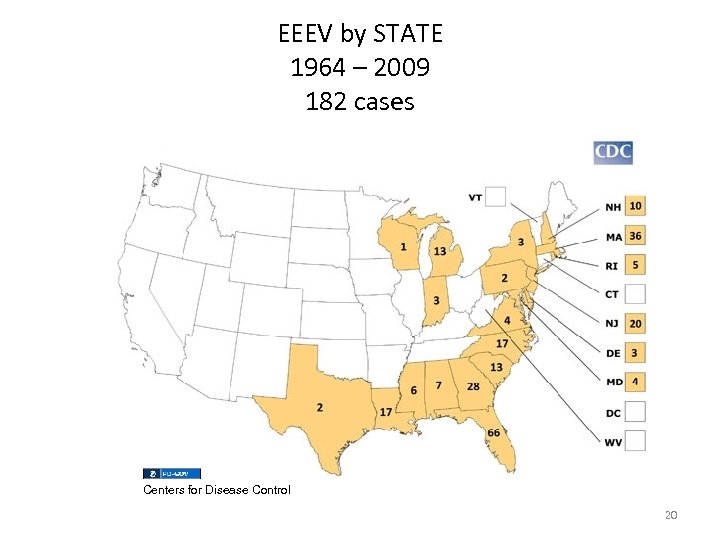

EEEV by STATE 1964 – 2009 182 cases Centers for Disease Control 20